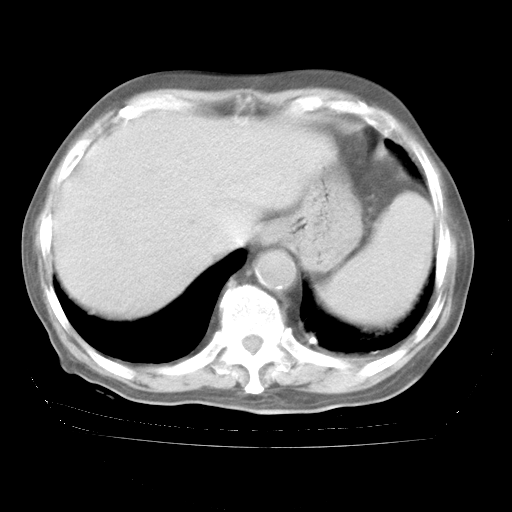

腹部B超:胆囊壁增厚,肝、胆、胰、脾、肾无异常,肠系膜淋巴结、腹膜后淋巴结无增大。